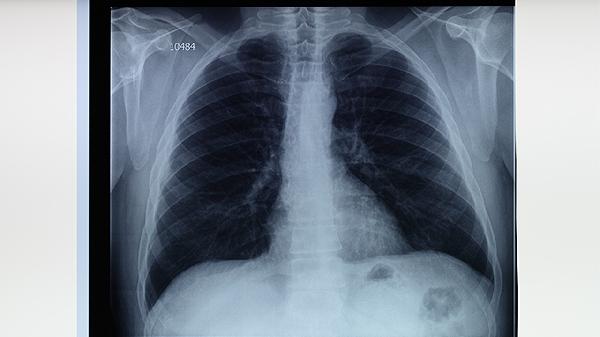

肺結(jié)核病情可通過(guò)規(guī)范用藥、營(yíng)養(yǎng)支持、隔離防護(hù)、適度運(yùn)動(dòng)及心理調(diào)節(jié)等方式有效緩解。肺結(jié)核是由結(jié)核分枝桿菌感染引起的慢性傳染病,主要累及肺部,需長(zhǎng)期綜合干預(yù)。

肺結(jié)核患者需嚴(yán)格遵醫(yī)囑使用抗結(jié)核藥物,常用方案包括異煙肼片、利福平膠囊、吡嗪酰胺片、乙胺丁醇片等聯(lián)合用藥。全程規(guī)律服藥6-9個(gè)月可殺滅結(jié)核菌,避免耐藥性產(chǎn)生。治療期間須定期復(fù)查肝功能、胸片等監(jiān)測(cè)療效,不可自行減藥或停藥。

肺結(jié)核患者需保持規(guī)律作息,每日睡眠不少于7小時(shí)。注意氣候變化及時(shí)增減衣物,預(yù)防呼吸道感染。治療期間若出現(xiàn)皮膚黃染、視力模糊等藥物不良反應(yīng),應(yīng)立即就醫(yī)調(diào)整方案。完成全程治療后仍需每年復(fù)查胸片,監(jiān)測(cè)復(fù)發(fā)可能。均衡飲食結(jié)合適度運(yùn)動(dòng)有助于加速康復(fù)進(jìn)程。